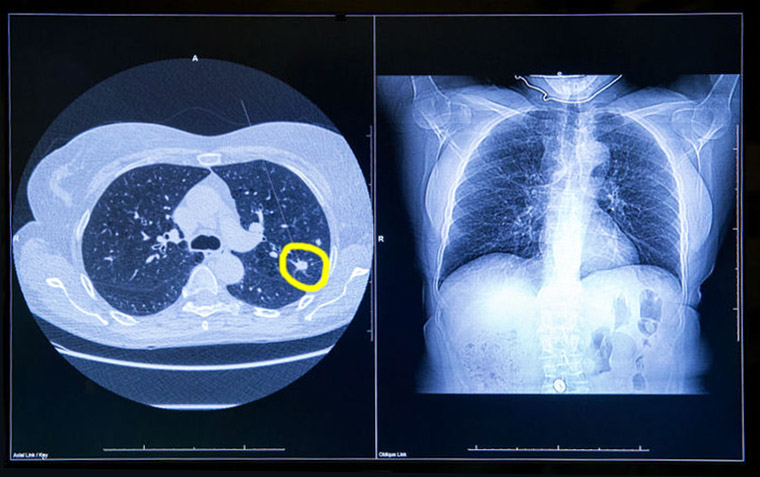

Del total de participantes, el 12,4% recibió un diagnóstico de cáncer de pulmón en el plazo de un año. Se realizaron procedimientos invasivos al 16,2% de todos los participantes y al 7,3% de aquellos sin cáncer de pulmón eventual. Alrededor del 60% de los participantes recibió atención acorde con las directrices, y aproximadamente un tercio recibió cuidados menos intensivos. Las tasas de procedimientos invasivos en aquellos sin cáncer fueron bajas. Annals of Internal Medicine, diciembre de 2025.

En las personas que se sometieron a una TC de tórax de baja dosis para la detección del cáncer de pulmón, la presencia de calcio en la arteria coronaria fue un predictor independiente de muerte por cualquier causa y eventos cardiovasculares, incluso después del ajuste por muerte no cardiovascular. Canadian Medical Association Journal, 2 de diciembre de 2024.

Este estudio demostró la viabilidad y eficacia del cribado del cáncer de pulmón en un contexto de la vida real, en el que la mayoría de los cánceres de pulmón se diagnostican en una etapa temprana y se extirpan quirúrgicamente. Nuestros resultados también destacaron la importancia de la participación en cada ronda, subrayando el hecho de que optimizar la organización es un objetivo principal. eBioMedicine, noviembre de 2024.

Se ha registrado un cambio desde la introducción del rastreo de cáncer de pulmón hacia mayor número de diagnósticos de cáncer de células no pequeñas en estadio I, lo que coincide con un aumento en la  supervivencia. Sin embargo, los pacientes que no eran blancos y los que vivían en áreas de mayor privación tenían una menor tasa de detección en estadio I, lo que destaca la necesidad de esfuerzos para aumentar el acceso a las pruebas de detección en los EE. UU. British Medical Journal, 30 de marzo de 2022.

Los resultados del estudio británico UKLS muestran reducción de la mortalidad por cáncer de pulmón a partir del rastreo en pacientes de alto riesgo con una única tomografía computada de baja dosis. Un metaanálisis de nueve ensayos aleatorios proporciona un apoyo inequívoco para la detección del cáncer de pulmón en grupos de riesgo identificados. The Lancet Regional Health Europe, 11 de septiembre de 2021.